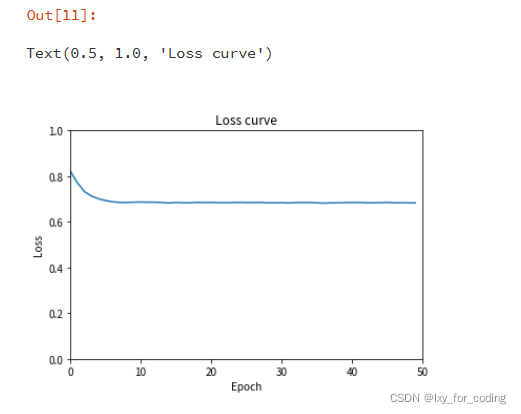

step4:模型训练

num_epochs = 50#机器较差 仅训练10个epoch

#可视化训练过程中损失变化

plt.xlim(0, len(losslist))

plt.xlabel("Epoch")

plt.ylabel("Loss")

plt.ylim(0, 1)

plt.plot(losslist)

plt.title('Loss curve')